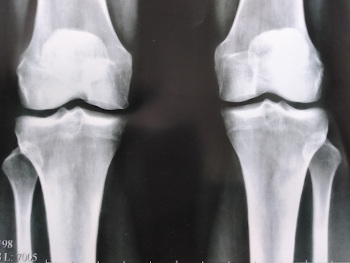

Endoproteza koljenskog zgloba, fotografija.